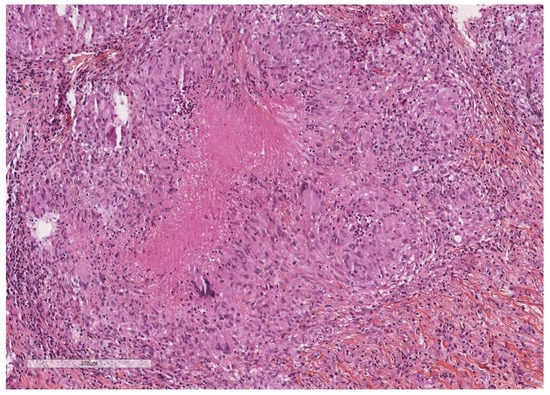

- Karpathiou, G.; Hathroubi, S.; Patoir, A.; Tiffet, O.; Casteillo, F.; Brun, C.; Forest, F.; Rahman, N.M.; Peoc’h, M.; Froudarakis, M.E. Non-specific pleuritis: Pathological patterns in benign pleuritis. Pathology 2019, 51, 405–411. [Google Scholar] [CrossRef] [PubMed]